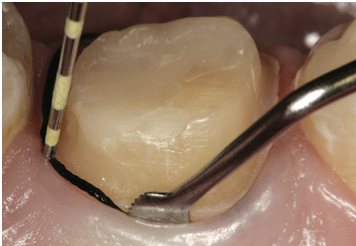

Tissue management is another key step in the fixed prosthodontic landscape. Gingival retraction cords remain the most commonly practiced procedure for tissue management. The goal is to achieve a V-shaped sulcus at a 0.2-mm minimum width, whether a single cord or double cord technique is used. The V-shaped sulcus with a 0.2-mm width creates access for the wash or syringe material so that enough volume may be placed into the desired area and removed in one piece without tearing (Figure 4).

Fig 4. A V-shaped sulcus with a 0.2-mm width is required for access for the wash or syringe material.

Figure 4